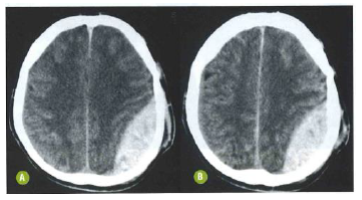

A seguinte tomografia computadorizada de crânio evidencia